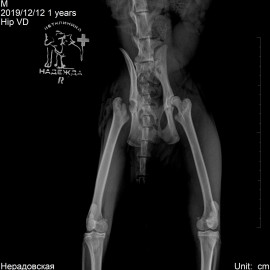

Наш пациент из города Котлас, кот по кличке Кузьма. Первый раз обратились в нашу клинику с жалобами на хромоту на заднюю левую лапу в течение 2 недель. Был проведен осмотр с проведением рентгенологического исследования (снимок 1). Был поставлен диагноз: перелом шейки правого бедра. Была проведена операция - резекционная артропластика правого тазобедренного сустава (снимок 2).